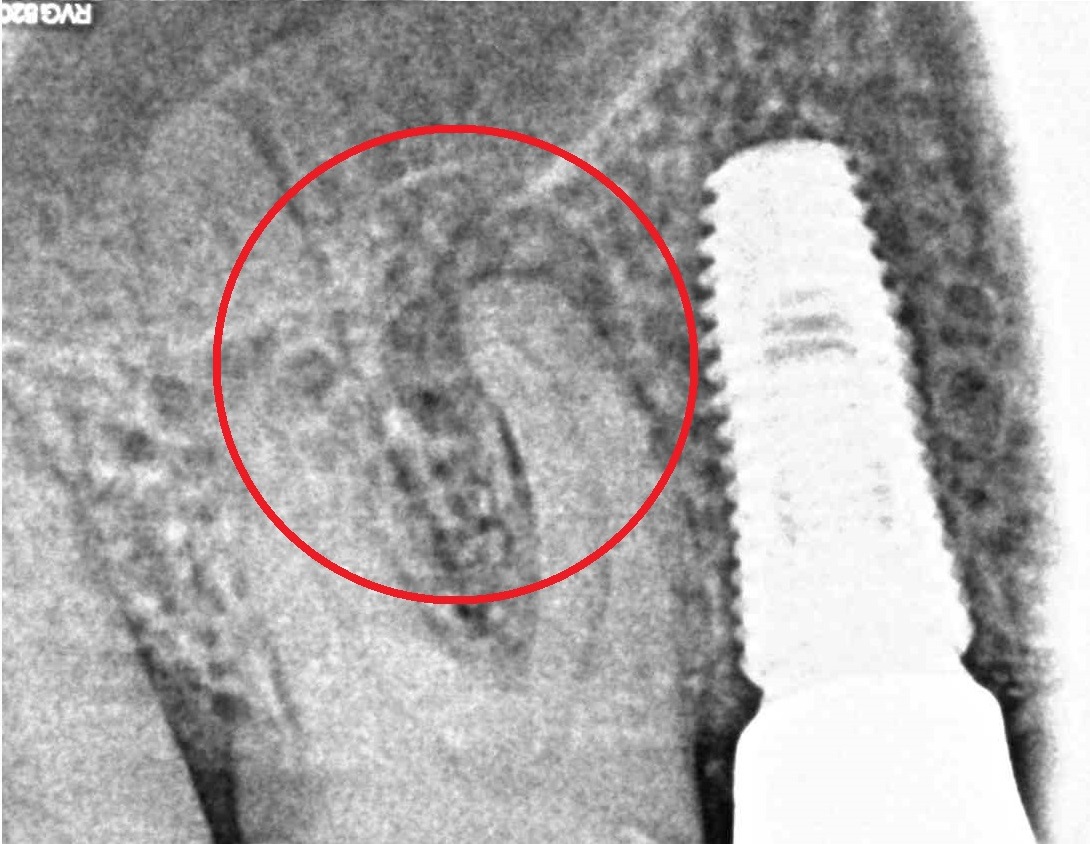

- Лечение периодонтита

Проблема

Пациент обратился в клинику с постоянными ноющими болями усиливающимися при накусывании.Решение

В нескольких клиниках было предложено удаление данного зуба. В нашей клинике такие зубы лечат. Пациенту было проведено эндодонтическое лечение данного зуба. Результат положительный, идет восстановление костной ткани.Оставьте заявку - перезвоним в течении 15 минут!